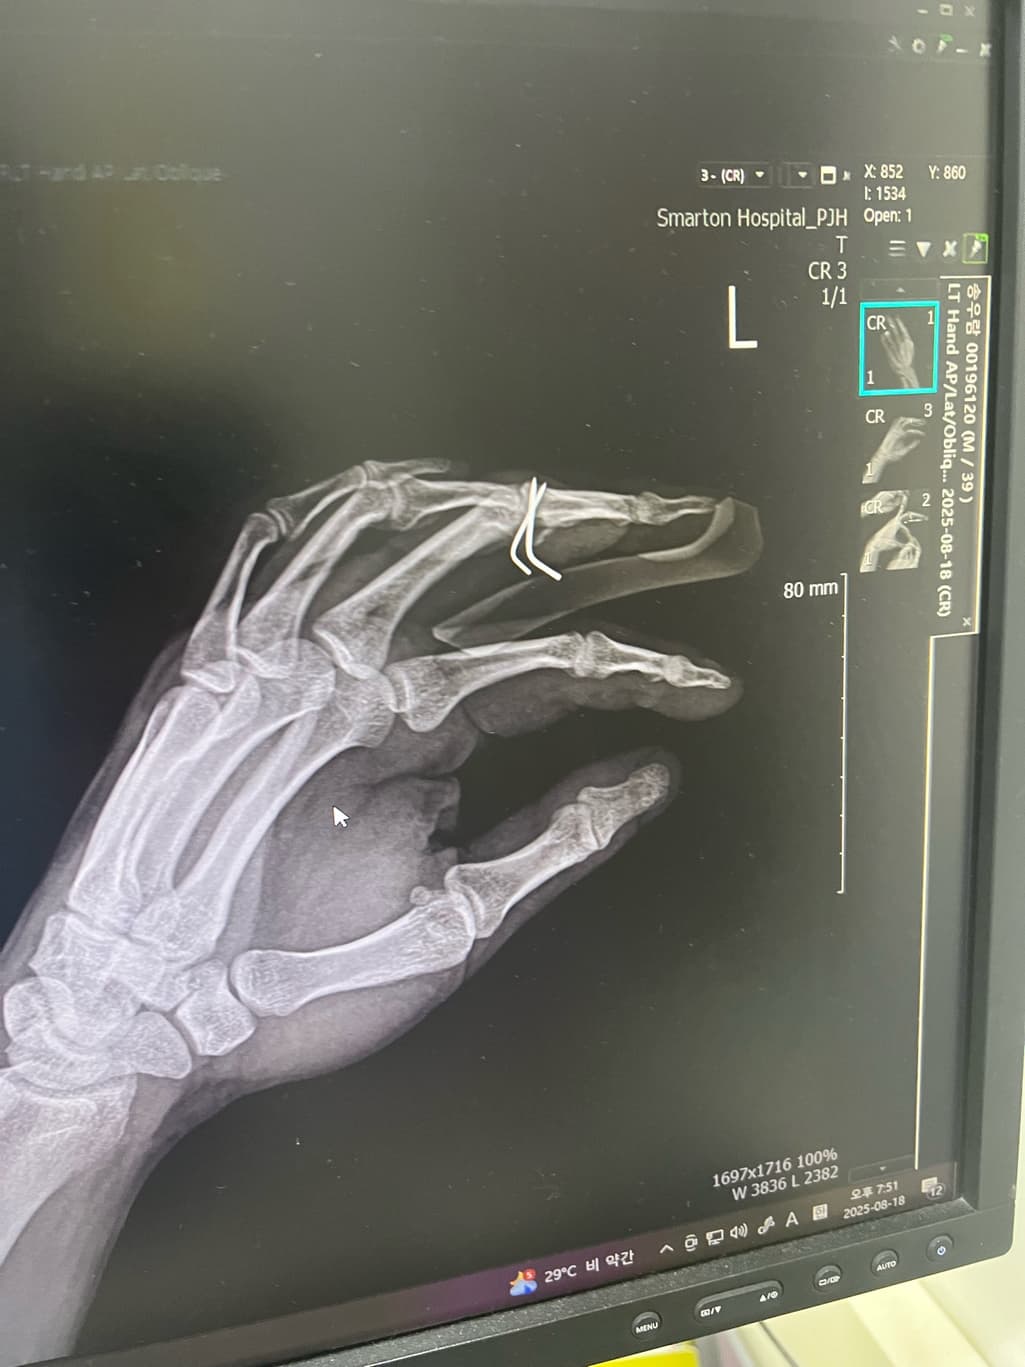

손가락 골절 수술 후 핀제거 했습니다.

1. 핀 제거를 하는데 원래 이렇게 아프게 뽑나요? 집도하신 원장님이 엑스레이 사진 빨간방향으로 잡아 땡기시더라구요.

그래서 제가 “그쪽방향이 아니다” 하니까 반대방향으로 빼던데 이사람이 집도한거 맞나요? 엑스레이도 봣으면서 왜 저 빨간방향으로 땡기는지.. 엄청아팟고 상처가 커졌습니다.

보통 핀을 뽑을 땐 약간의 통증이 동반되는것은 맞지만 핀을 박았을 때의 각도와 핀이 박힌 방향 그대로 빼는것이 맞지만 "ㄴ" 모양으로 되어있기에 다소 뽑을 때 통증이 동반됐을 가능성이 높습니다.